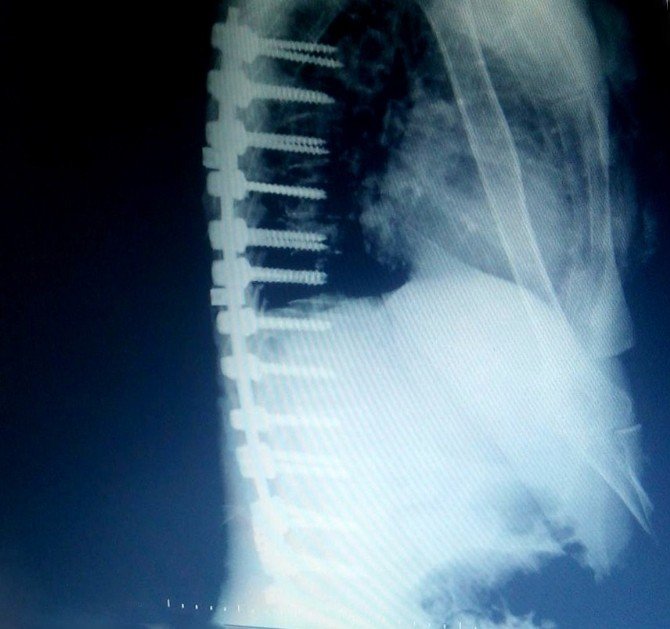

"Hasta bana geldiğinde ayağa kalkmada ve yürümede çok zorlanıyor ve ayakta dik olarak duramıyordu. Yapılan tomografi ve mr sonucunda t6, t9, t12, l1, l2, l3 omurga kemiklerinde çökme ve patlama kırıkları olduğunu gördük. Hastaya operasyonla sırt (torakal) ve bel (lomber) omurgalarına titanyum vida ve plak sistemi ile yeni bir omurga desteği sağlayacağımızı karalaştırdık. Kemik erimesinin ileri derecede olması sırt omurgalarını başlangıcından vida işleminin yapılacağından ileri derecede riskli olduğu aşikardır. Bu durumlarda çok ender olarak operasyon kararı alınabilmektedir. Operasyon 3 saat sürdü. Hastaya 26 titanyum vida ile prod sistemiyle yeni bir omurga desteği sağlayarak hastanın ayakta durmasını ve yürümesini sağlayan yeni bir iskelet destek sistemi oluşturduk. Operasyondan sonraki 3. gününde hastayı yürüttük. Hastanın ve ailenin mutluluğu görülmeye değerdi. 4. günü hastayı taburcu ettim. Tabi henüz her şey bitmedi. Yaranın iyileşmesi ve uygulanan platin ve vidaların kemikle kaynaşması için en az 3 aylık bir zamana daha ihtiyacımız var. Hasta tedavimiz altında ve kontrolümüzde kalmaya devam ediyor."